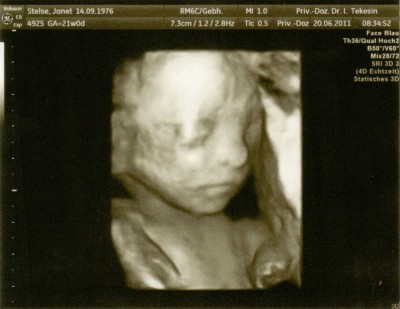

Teddylove09-wie weit bist Du denn? Und Du weißt also auch noch nicht was "es" wird? Also ich bin heute 20+6 und weiß es auch noch nicht! Bin doch sooooo neugierig und kann es kaum abwarten. Ich finde wir sind spät dran mit dem Outing und ich habe nicht gerade HIER geschrien, als Geduld verteilt wurde.

Hier ist außer unfassbarer Stress alles super. Baby wächst und gedeiht und ist seeehr aktiv! Tritt mich täglich mehrfach

Ich hab auch schon ne ordentliche Murmel